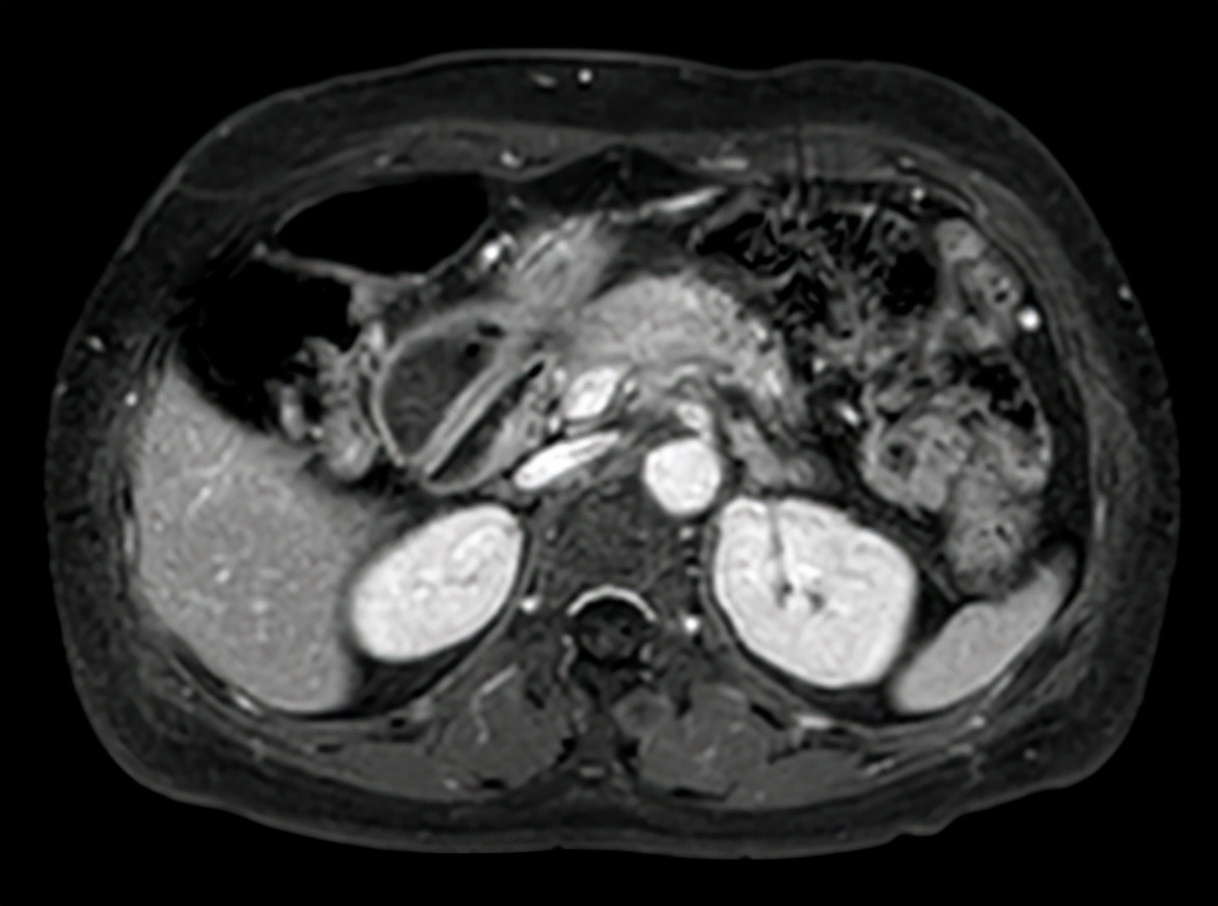

入院以后还需要进一步了解肿瘤的大小、部位、是否有侵犯到其他器官等,完善了腹部增强CT、胸部CT和超声胃镜等检查。CT胸部平扫(2019-08-16 13:21):左肺微小结节,左肺纤维灶。CT上腹部平扫+增强(2019-08-20 16:39):胰腺颈体部胰腺癌伴脾动脉受侵考虑,脾静脉可疑受侵。 腹膜后多发稍肿大淋巴结。MR(磁共振)上腹部平扫+增强+MRCP(2019-08-17 15:49):胰腺颈体部占位(考虑胰腺癌),病变侵犯脾血管、腹腔干分叉部;腹膜后多发稍肿大淋巴结。ES(内镜)超声胃镜(2019-08-21 15:20):胰颈低回声病灶。

2019-10-06上腹部增强MRI